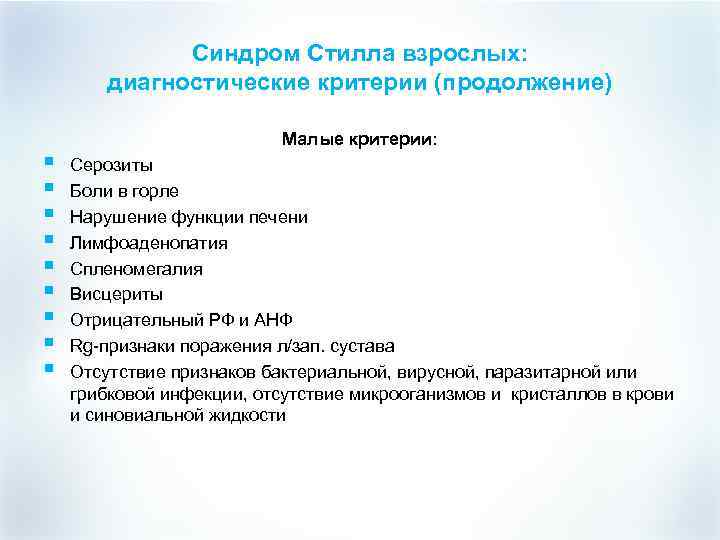

Синдром Стилла взрослых: диагностические критерии (продолжение) § § § § § Малые критерии: Серозиты Боли в горле Нарушение функции печени Лимфоаденопатия Спленомегалия Висцериты Отрицательный РФ и АНФ Rg-признаки поражения л/зап. сустава Отсутствие признаков бактериальной, вирусной, паразитарной или грибковой инфекции, отсутствие микрооганизмов и кристаллов в крови и синовиальной жидкости

Синдром Стилла взрослых: диагностические критерии (продолжение) § § § § § Малые критерии: Серозиты Боли в горле Нарушение функции печени Лимфоаденопатия Спленомегалия Висцериты Отрицательный РФ и АНФ Rg-признаки поражения л/зап. сустава Отсутствие признаков бактериальной, вирусной, паразитарной или грибковой инфекции, отсутствие микрооганизмов и кристаллов в крови и синовиальной жидкости